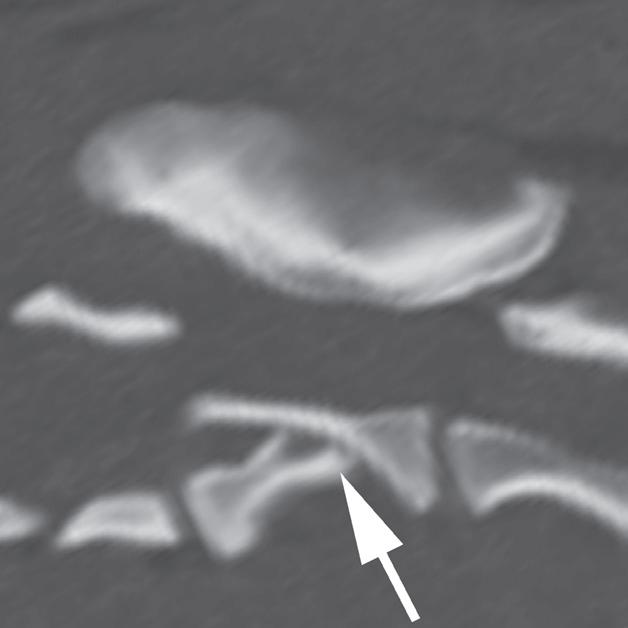

Badanie wykonano u 5-letniego, kastrowanego kota rasy europejskiej po urazie o nieznanej przyczynie, do którego doszło w ciągu 48 godzin poprzedzających badanie. U kota stwierdzono liczne złamania czaszki typowe dla urazów o dużej sile. Prezentowane obrazy ułożono w kolejności od donosowej do doogonowej. Urazy obejmują: złamanie lub zwichnięcie w obrębie kości nosowych i szczękowych (a – strzałka), separacje spojenia żuchwy (b – strzałka), złamania wyrostków pionowych kości podniebiennych (c – strzałki), rozejście spojenia podniebiennego (c – grot strzałki), złamania kości skrzydłowych (d – strzałki), doogonowe zwichnięcie prawego wyrostka kłykciowego (e – grot strzałki) oraz złamanie przez wyrostek jarzmowy lewej kości skroniowej (e – strzałka)